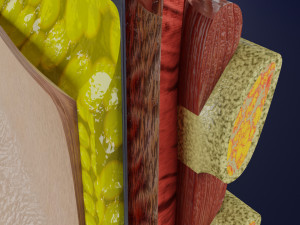

This is a 1:1 scaled model of right breast cut opened in sagittal plane to reveal its internal antomy and histology (schematic). The deeper parts and fascial layers are also depicted to give a very detailed approach to the model. The full layers starting from skin, nipple areola, till intercodtal muscles and ribs are also depicted.